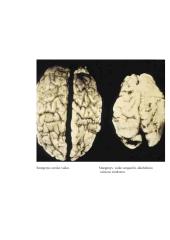

Alkoholio vartojimas gali būti savaiminių persileidimų, placentos atšokos, priešlaikinio gimdymo priežastis. Dėl alkoholio poveikio vaisiui galimas įvairaus laipsnio ir pobūdžio pažeidimas. Sunkiausias yra vaisiaus alkoholinis sindromas, kuriam būdingi simetriškas vaisiaus augimo atsilikimas, centrinės nervų sistemos pažeidimas (įvairūs neurologiniai , intelekto vystymosi sutrikimai ar atsilikimas, galvos apimties sumažėjimas), charakteringa veido deformacija (siauri akių plyšiai, pailgėjusi vidurinė veido dalis, plokščias viršutinis žandikaulis).Dažniau pasitaiko lengvesnio laipsnio su alkoholiu susijusių nervų sistemos pažeidimų (atminties ,dėmesio, adaptacijos problemos, kalbos ir matematinių sugebėjimų specifiniai sutrikimai) ar su alkoholiu susiję gimimo defektai (šlapimą išskiriančių organų sutrikimai, širdies ir kaulų sistemų apsigimimai įvairūs regėjimo ir klausos defektai).Tačiau mokslinių tyrimų išvados dėl alkoholio, priešingai nei rūkymo, ne tokios griežtos: tik daugiau nei 160 g gryno alkoholio suvartojimas per savaitę (apie 10 l nestipraus alaus ar 20 mažų vyno taurių)nėštumo metu susijęs su vaiko intelekto sumažėjimu .Vis dėl to rekomenduojama nėščioms moterims būti labai atsargioms vartojant alkoholį ir neviršyti saugios dozės( 1 maža vyno taurė,0,5 nestipraus alaus) per dieną.